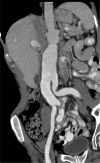

Results: Of the 160 IgG4-RD patients in this cohort, 36 (22.5%) had large-vessel involvement. The mean age at disease onset of the patients with large-vessel IgG4-RD was 54.6 years. Twenty-eight patients (78%) were male and 8 (22%) were female. Thirteen patients (36%) had primary IgG4-related vasculitis and aortitis with aneurysm formation comprised the most common manifestation. This affected 5.6% of the entire IgG4-RD cohort and was observed in the thoracic aorta in 8 patients, the abdominal aorta in 4, and both the thoracic and abdominal aorta in 3. Three of these aneurysms were complicated by aortic dissection or contained perforation. Periaortitis secondary to RPF accounted for 27 of 29 patients (93%) of secondary vascular involvement by IgG4-RD. Only 5 patients demonstrated evidence of both primary and secondary blood vessel involvement. Of those treated with rituximab, a majority responded positively.

Conclusions: IgG4-RD is a distinctive, unique, and treatable cause of large-vessel vasculitis. It can also involve blood vessels secondary to perivascular tumefactive lesions. The most common manifestation of IgG4-related vasculitis is aortitis with aneurysm formation. The most common secondary vascular manifestation is periaortitis with relative sparing of the aortic wall. Both primary vasculitis and secondary vascular involvement respond well to B cell depletion therapy.